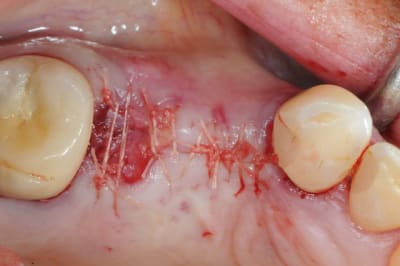

pour débuter ce post je propose un petit cas avec une ROG un comblement alvéolaire et un lambeau pédiculé pour fermer le site d'extraction.

au début incision supra crestal puis lambeau muco-périosté.

avec une simple lame 11 qui tranche le long de gencive palatine. évidemment c'est le plus dure à faire pour éviter de transpercer ou d'avoir d'un coté ou de l'autre une épaisseur trop faible.

toutefois je préfère que le lambeau soit pédiculé plutôt que libre. et vous ??